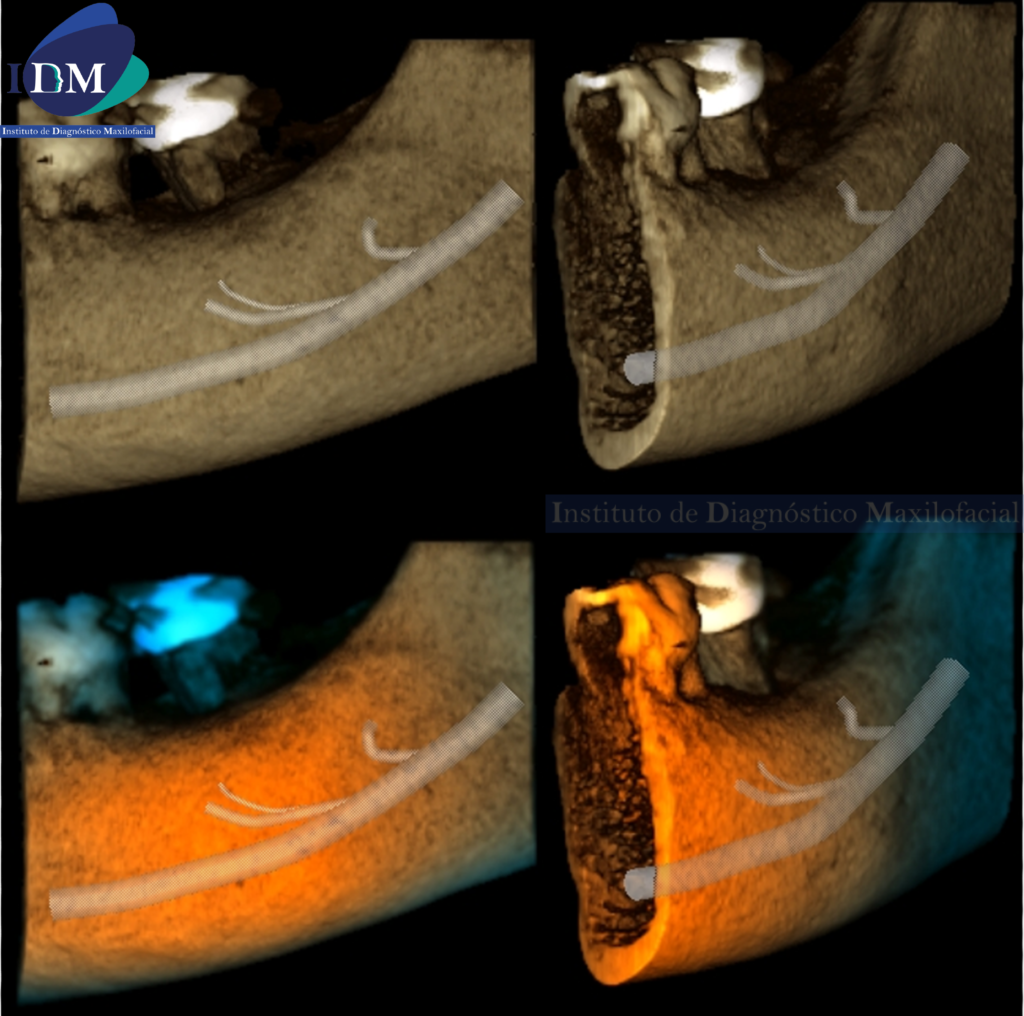

RECONSTRUCCIÓN 3D

Variante anatómica del conducto dentario inferior izquierdo.

La bifurcación del conducto dentario inferior (BCDI) es una variante anatómica del canal mandibular donde anatómicamente se observa dicho conducto dividido en dos ramas, cada una separada en su propio canal por donde discurre una rama neurovascular que puede ser observado en diferentes formas; puede presentarse tanto en un solo lado de la rama mandibular como en ambos lados. Un estudio realizado por el investigador Fukami et al., observaron la presencia de conductos mandibulares bífidos en cadáveres por

medio de tomografía computarizada volumétrica y realizó cortes histológicos evidenciando que dichos conductos contenían haces de nervios y arterias de diversos tamaños.

Reconocer la ubicación y configuración del conducto dentario inferior es importante en cualquier tipo de cirugía bucal que implique procedimientos en la mandíbula, tales como la extracción del tercer molar, implante dental y osteotomía sagital de rama. Existen muchos casos de fracaso en el bloqueo del nervio dentario inferior por la presencia del conducto mandibular bífido